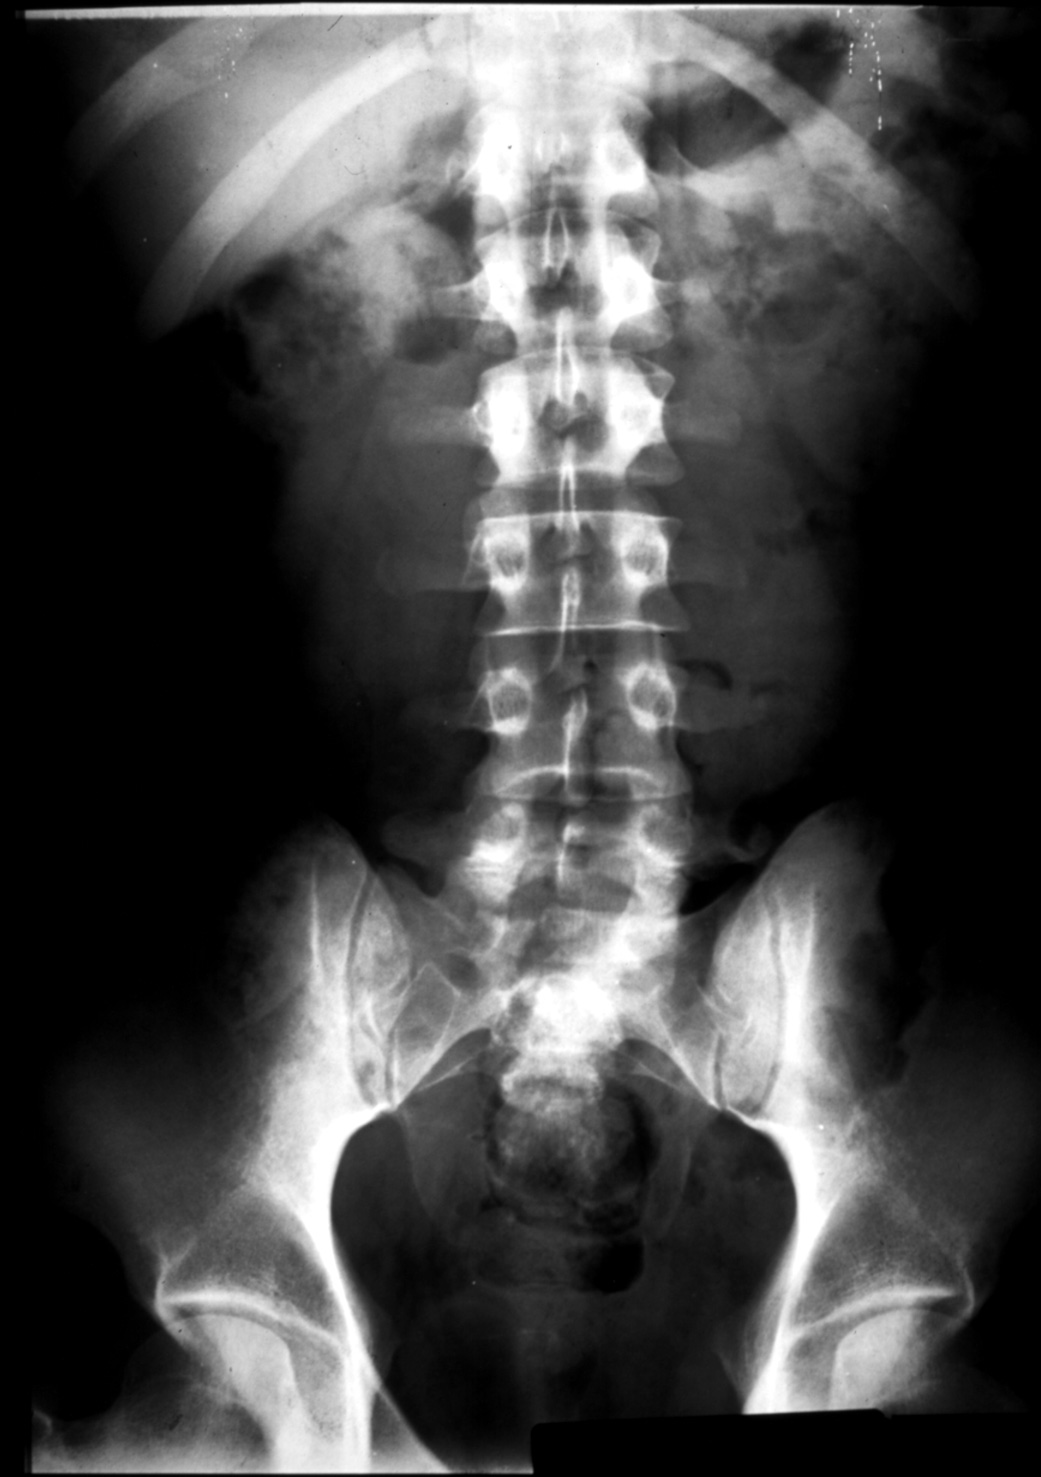

The Structural Basis of Medical Practice

The Pennsylvania State University ©2000

College of Medicine